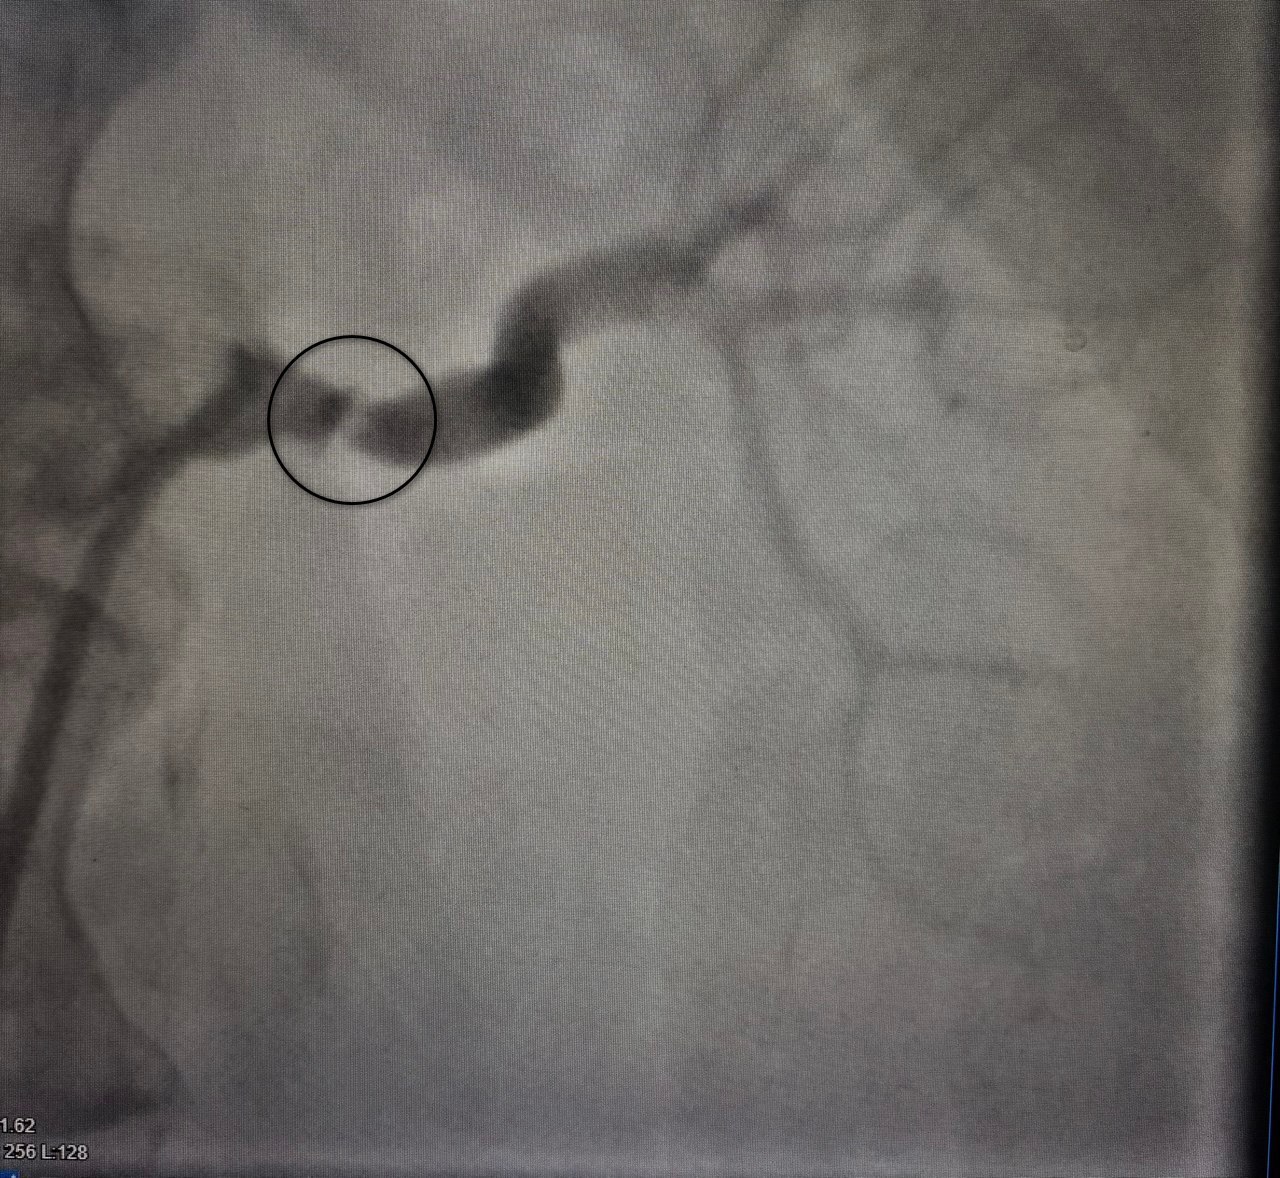

После постановки диагноза пациентку перевели в областную больницу №1, где под контролем врача-рентгенхирурга Ивана Тимошина ей выполнили баллонную ангиопластику и стентирование пораженной артерии. Это малоинвазивное вмешательство позволило восстановить кровоток. Состояние пациентки значительно улучшилось: давление стабилизировалось на нормальных значениях, что позволило снизить лекарственную нагрузку. Через год на профилактическом осмотре в Воронежской городской клинической больнице №3 она чувствовала себя хорошо, подтвердив долгосрочный успех лечения.